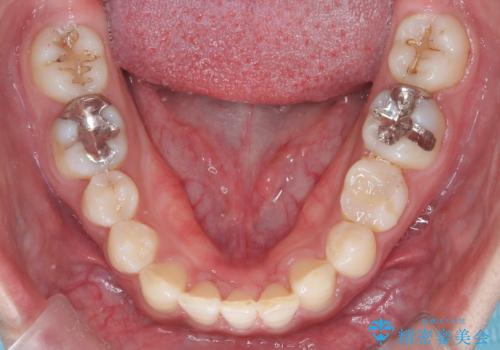

【インビザライン】空隙歯列の矯正

単純に前歯の隙間の閉鎖をしてしまうと、前歯に早期接触が生まれ、臼歯が噛まなくなってしまいます。適切な治療計画を立てることで、噛み合わせも良好な結果を得ることができました。